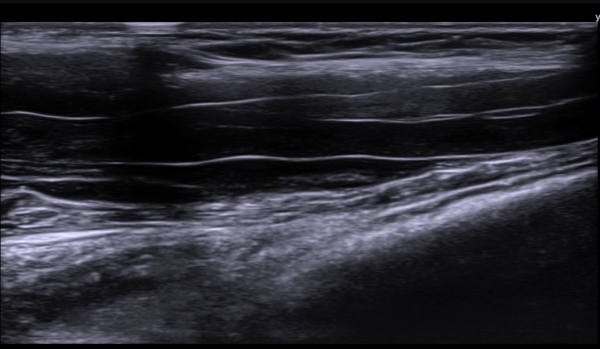

ÃÊÀ½ÆÄ  °Ë»ç  : À­ÆÈ ±ÙÀ§ºÎ Á¤Áß ½Å°æ Ⱦ´Ü¸é°Ë»ç¿¡¼­ Á¤Áß ½Å°æÀÇ ºÎÁ¾°ú ÀϺΠ½Å°æ¼¶À¯ÀÇ Àú¿¡ÄÚ ºÎÁ¾ÀÌ °üÂûµÈ´Ù

(»çÁø 1, 2). ŽÃËÀÚ¸¦ Á¶±Ù ´õ ±ÙÀ§ºÎ·Î À̵¿ÇÏ´Ï Á¤Á߽ŰæÀÇ Àú¿¡ÄÚ ºÎÁ¾ÀÌ °üÂûµÈ´Ù(»çÁø 3, 4).